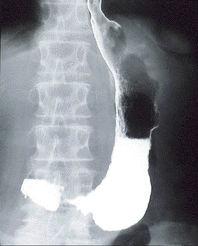

Diffuse inflammatory gastric disease resembling scirrhous advanced stomach cancer.

Inflammatory or ulcerative disease / lesions/Others

Stomach/More than one of above

X-ray